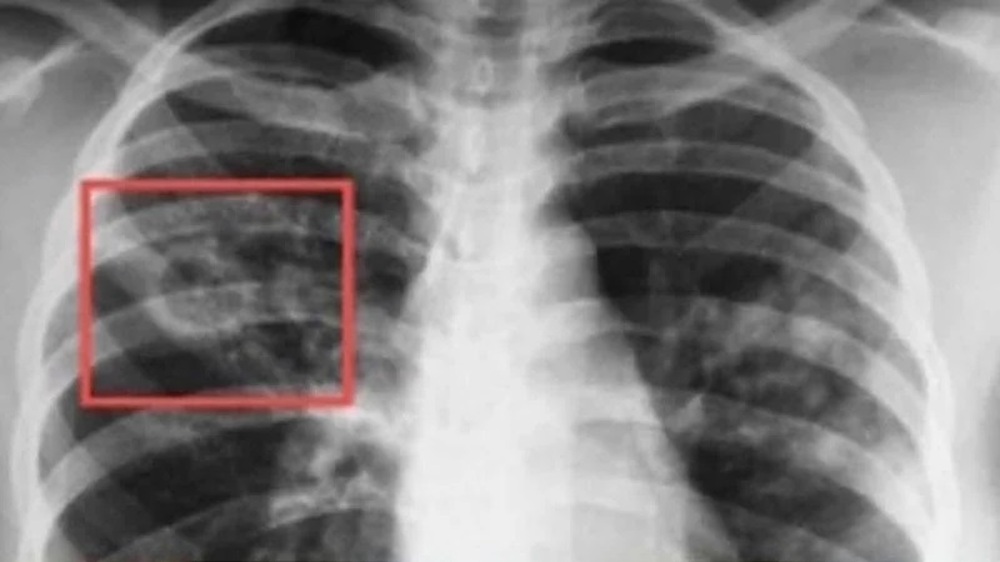

В България диагностиката, лечението и профилактиката на туберкулозата са безплатни за всички, които се нуждаят, независимо от техния здравноосигурителен статус, посочват на сайта си от Националния център по заразни и паразитни болести. По инициатива на Световната здравна организация, всяка година на 24 март се отбелязва Световният ден за борба с туберкулозата. Това е възможност за повишаване на осведомеността на населението за тежестта на болестта в национален и световен мащаб и за подобряване на усилията за грижа и превенция. Датата е избрана в чест на първото научно съобщение, направено от д-р Робърт Кох, който на 24 март 1882 г. обявява, че е открил причинителя на туберкулозата – бактерията Mycobacterium tuberculosis.